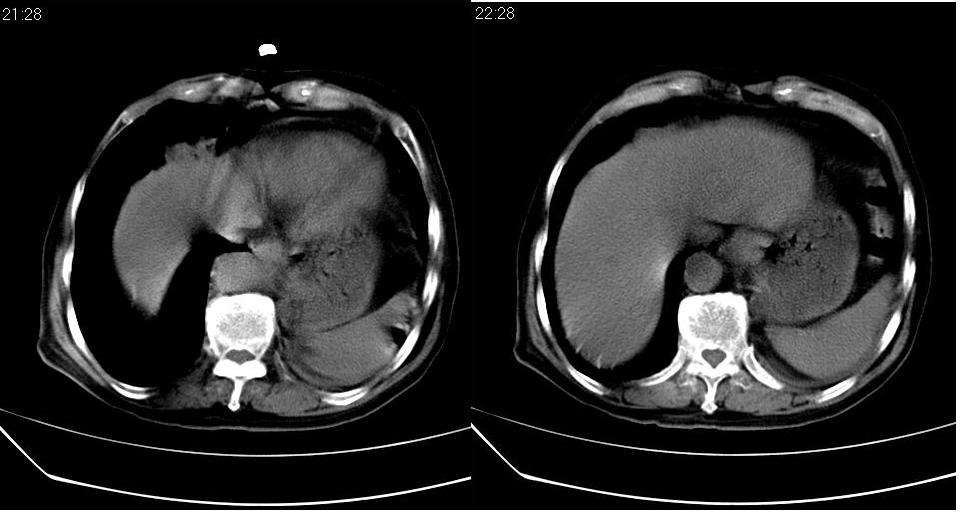

左肺下叶略萎陷、实变,内可见含气支气管征。左舌叶、中叶亦见少许斑片状高密度区,边界不清。纵隔未见肿大淋巴结影。

左下肺体积缩小,密度增高,见片增密影。边界模糊,见支气管充气像,肺门纵隔无异示,心脏气管左移,左侧胸腔少量积液。考虑肺部感染伴部分肺不张[有脑梗塞病史坠积性肺炎可能]

1、左肺下叶后基底段炎症并膨胀不全。

2、左侧胸腔积液。

3.两肺慢支改变。

左下肺体积缩小,密度增高,并见大片状致密影,边界模糊,其内见支气管充气像,肺门纵隔无异常,心脏气管左移,左侧胸腔少量积液。考虑:左肺炎性病变伴不张。